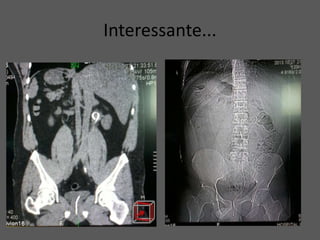

Interessante...

Calculo Ureteral